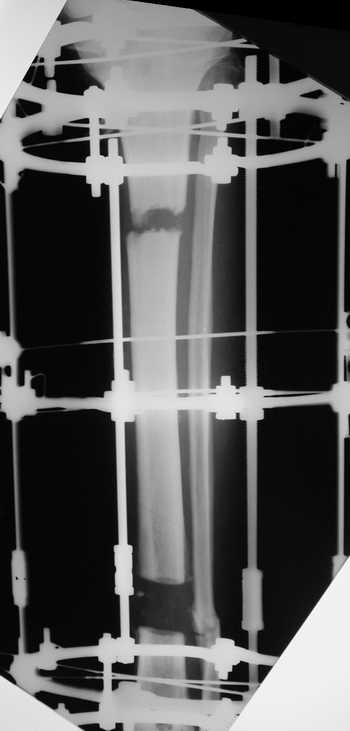

Мужчина, 33 года, резекция б\б кости по поводу остеомиелита после открытого

перелома. Стандартная методика билокального остеосинтеза (рис 1 и 2). В

конце удлинения выявилось неудовлетворительное взиморасположение

перемещенного фрагмента и дистального отломка (рис 3). Планирование (рис 4).

Адаптация отломков гексаподом за 5 дней (рис 5). Замена гексапода на обычные

штанги (рис 6 и 7)